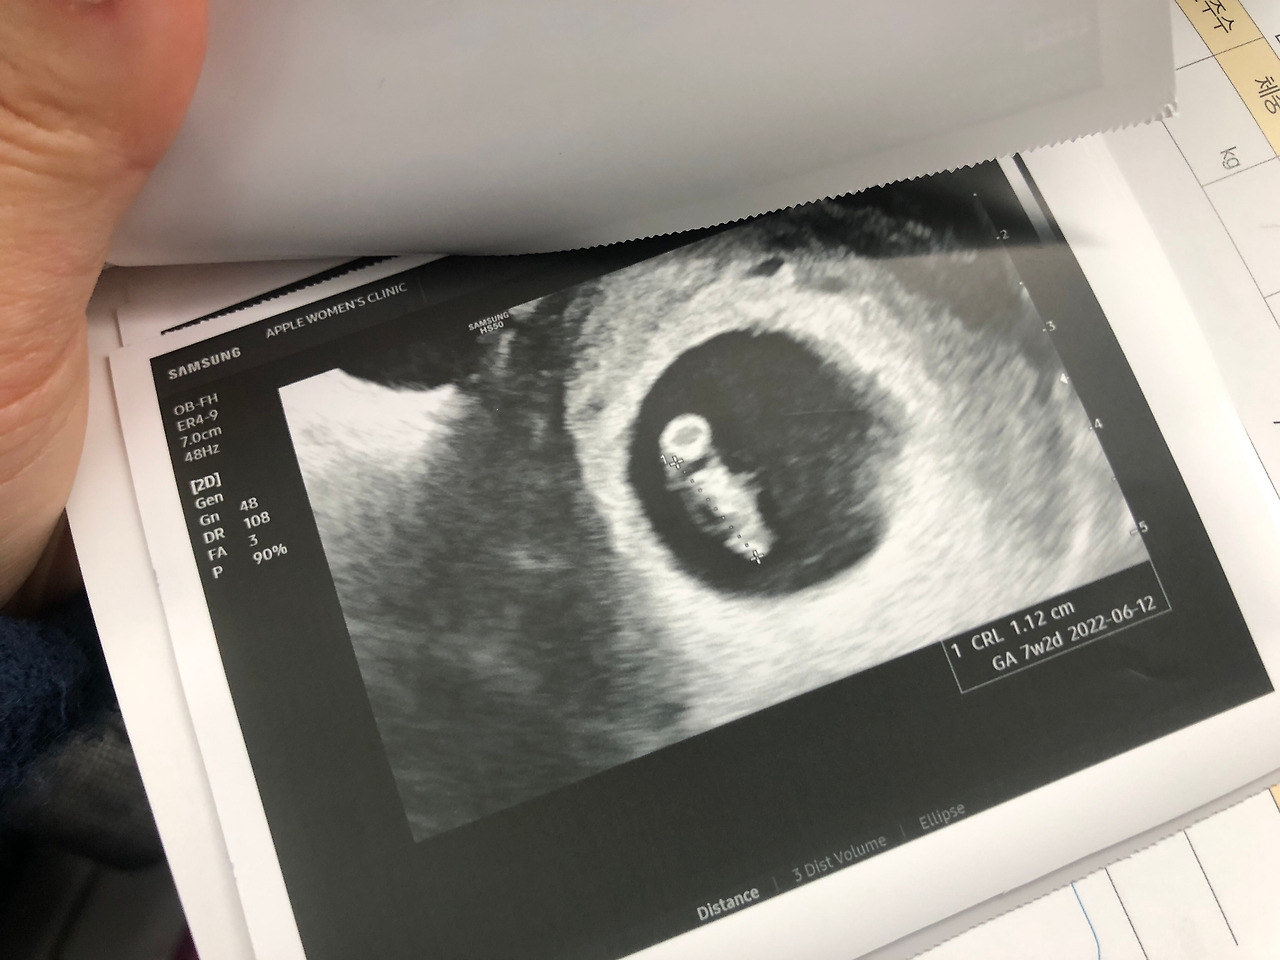

임신일기 6주 6일차

사실 좀 걱정했는데, 심장도 잘 뛰고 아주 잘 자라고 있더구나!